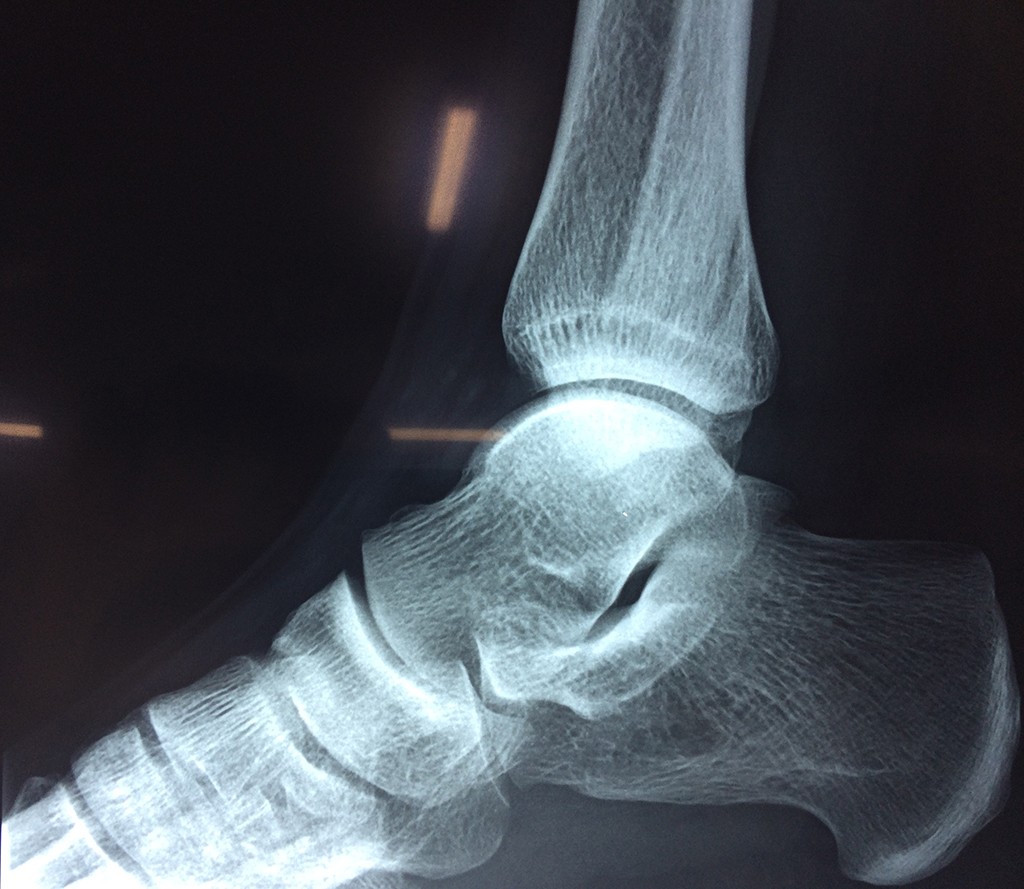

Una fractura de tobillo es la rotura de uno o más de los huesos del tobillo. Estas fracturas pueden ser:

Algunas fracturas de tobillo pueden requerir cirugía si:

- Los extremos de los huesos están desalineados entre sí (desplazados).

- La fractura se extiende hasta la articulación del tobillo (fractura intra-articular).

Cuando se necesita cirugía, es probable que esta implique el uso de clavijas de metal, tornillos o placas para sostener los huesos en su lugar mientras la fractura se consolida. Los elementos de soporte pueden ser temporales o permanentes.